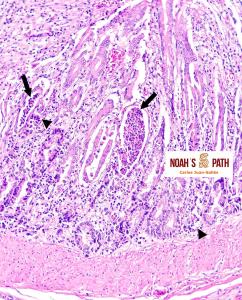

Estudio clínico-patológico e inmunohistoquímico de un brote de mortalidad en elands juveniles debido a infección intestinal por coronavirus en colaboración con Santiago Borragán del Parque de la Naturaleza de Cabárceno y Pepe Ramos de la University of Purdue.